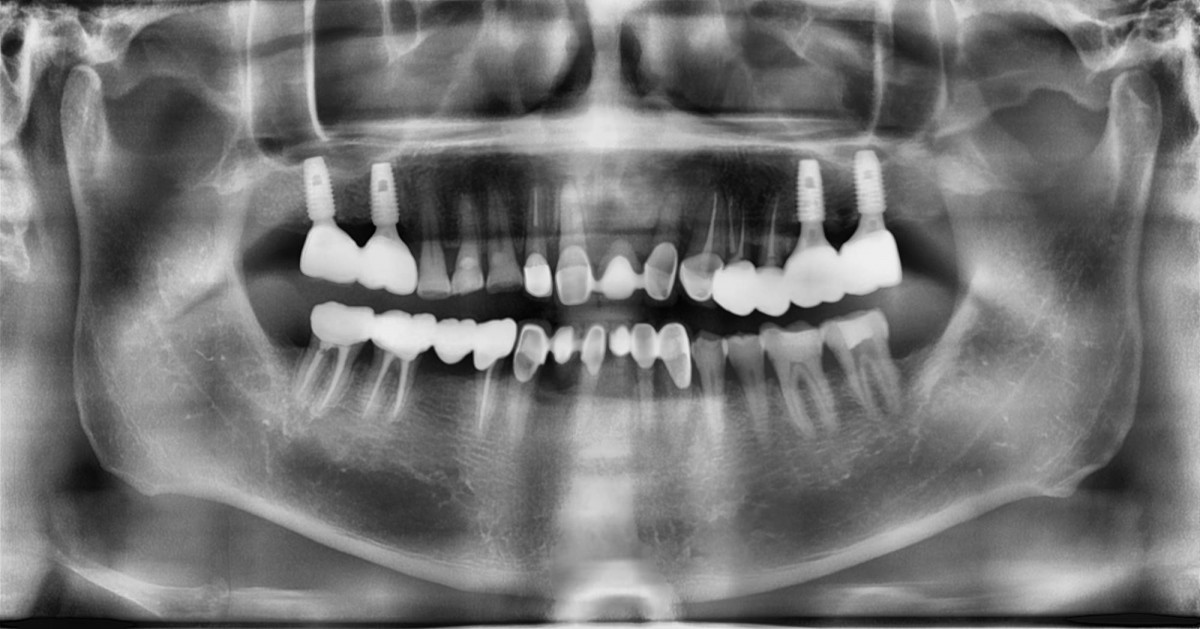

Socket Lift and Implant Placement in the right maxilla.

<GCacg> A 56-year-old male patient complained of pain in the right upper and lower jaws. And he wanted the upper first molar to be pulled out first.